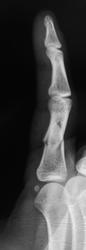

Ковырял с прокручиванием. Получил винтообразный перелом проксимальной фаланги.

Да не в шутке дело, суть то ее ПРАВИЛЬНАЯ))), действующая травмирующая сила имела в своем составе КРУТЯЩИЙ момент.

Здесь не чистое кручение, а кручение с изгибом кнаружи на что указывает дополнительная поперечная линия перелома.